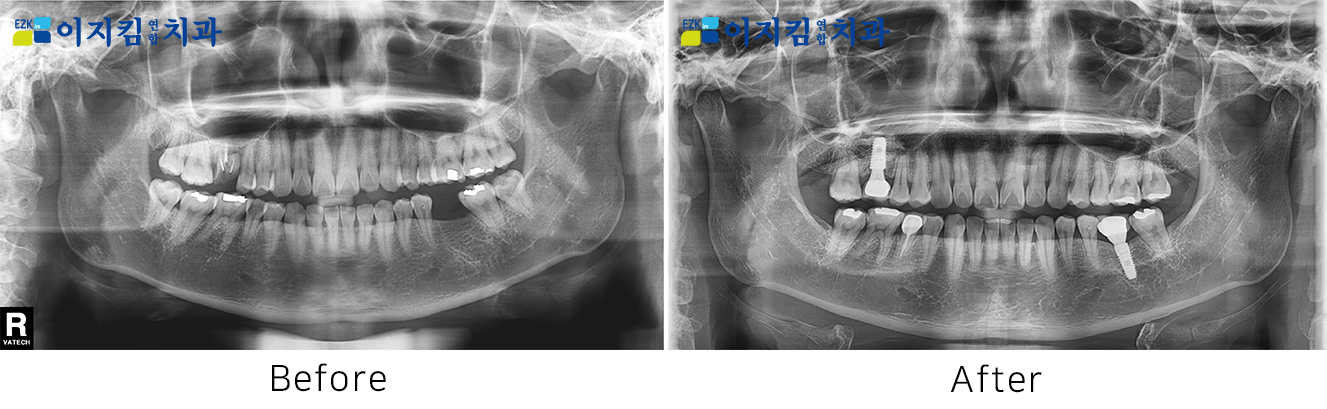

ÀÓÇöõÆ® Àü ¡¤ ÈÄ »çÁø

[

Á¶È¸¼ö : 2873

]